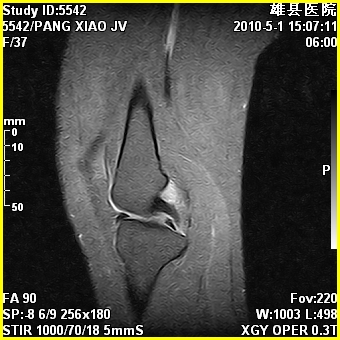

标题: MRI2894:患者右膝关节疼痛两月余,无明显外伤史 [打印本页]

标题: MRI2894:患者右膝关节疼痛两月余,无明显外伤史

右股骨下端前内侧类圆形异常信号,位于干骺端,呈长t1长t2改变,但信号不均,t1图上病灶中心见小片状稍高信号影,t2图上见散在稍低信号影,stir像呈高信号,因病灶较小,缺乏特征性改变,结合患者年龄及部位,考虑嗜酸性肉芽肿可能性大。胫骨关节面下的小囊状异常信号,如果一元论考虑则为嗜酸性肉芽肿,不过发生在这个部位的少见,二元论考虑为邻关节骨囊肿。半月板与前后交叉韧带均未见异常。

右股骨下端前内侧干骺端囊性良性病变,考虑 1内生软骨瘤 2骨囊肿 3肉芽肿。